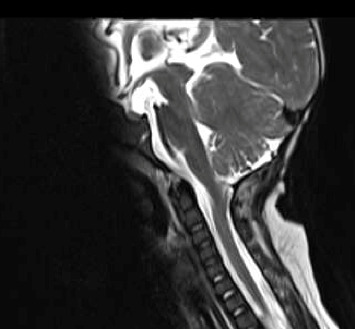

脊柱裂,特别是脊膜膨出,与自主神经功能障碍之间的联系是已知的,尽管罕见。本病例突出了脊髓脊膜膨出患儿继发的严重呼吸损害。我们描述了一个新生儿谁经历了严重的呼吸功能障碍后,成功的腰骶髓脊膜膨出修复在生命的第一天,在产前诊断为Arnold-Chiari II型畸形和先天性脑积水的背景下。此外,患者被发现有偶发脉络膜丛乳头状瘤,并在枕骨大孔减压术中切除。即使在多次成功的神经外科干预后,患者仍经历了多次需要插管和通气的呼吸暂停发作,并延长了重症监护病房的住院时间。尽管呼吸暂停-缺氧发作的频率异常高且严重,但患者表现出与年龄相适应的认知发展,现在通过气管切开术进行了夜间通气。围绕这些患者的多学科护理、呼吸窘迫的管理以及本病例的不同病因,我们可以吸取经验教训。尿路感染发作与呼吸暂停发作频率增加之间也存在相关性,这就提出了一个问题,即在有重要手术史的背景下,该患者的膀胱刺激是否部分触发了自主神经反射障碍。

The association between spina bifida, specifically myelomeningocele, and autonomic dysfunction is known although rare. This case highlights the severe respiratory compromise that can occur in paediatric patients secondary to myelomeningocele. We describe a case of a neonate who experienced profound respiratory dysfunction following a successful lumbosacral myelomeningocele repair on Day 1 of life, on the background of a prenatal diagnosis of Arnold-Chiari Type II malformation and congenital hydrocephalus. In addition, the patient was found to have an incidental choroid plexus papilloma which was resected along with foramen magnum decompression. Even after multiple successful neurosurgical interventions, the patient experienced a number of apnoeic episodes requiring intubation and ventilation and a prolonged intensive care unit stay. Despite the exceptionally high frequency and severity of the apnoeic-hypoxic episodes, the patient is demonstrating age-appropriate cognitive development and is now ventilated overnight via tracheostomy. There are lessons to be learnt surrounding the multidisciplinary care of these patients, management of respiratory distress, and the different aetiologies in this case. There was also a correlation found between episodes of urinary tract infection and increased frequency of apnoeic episodes, raising the question of whether her bladder irritation may be partially triggering her autonomic dysreflexia, on a background of a significant surgical history.